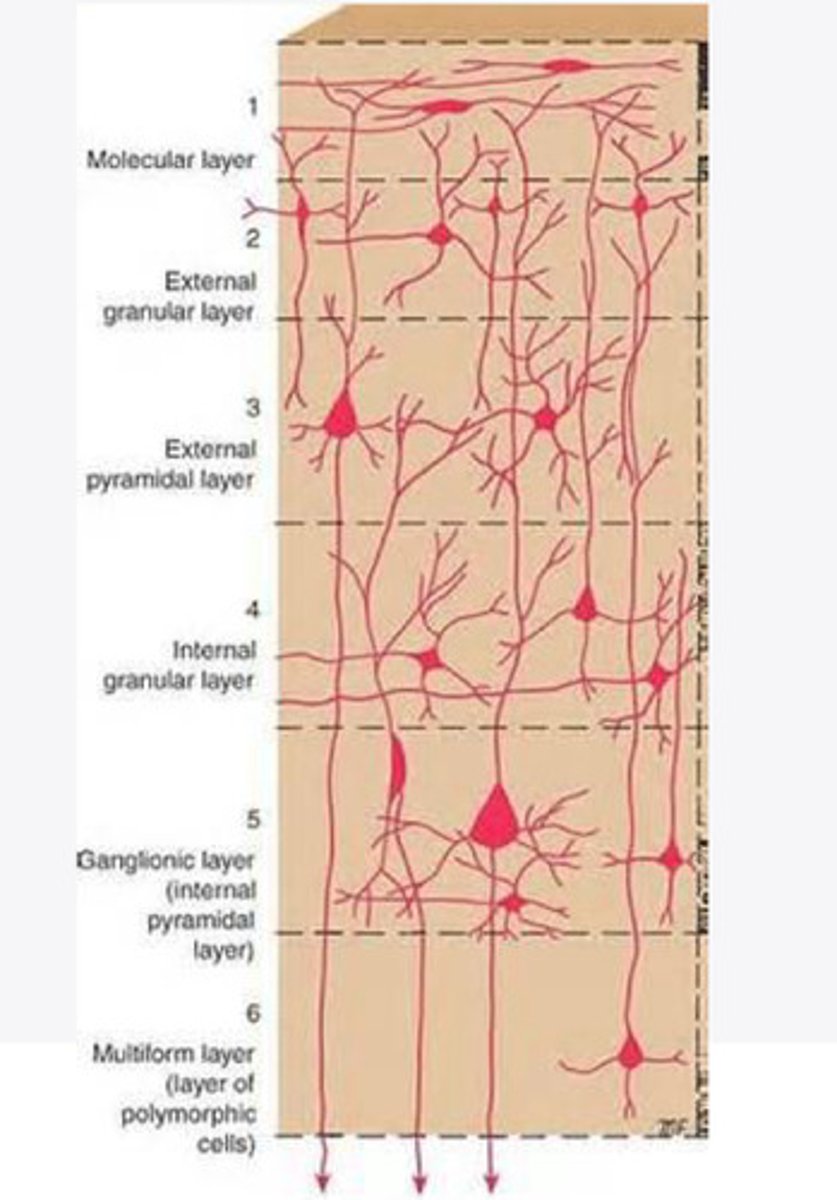

divided into 6 distinct layers, due to varying densities of cell body types within each layer

The cortex of the brain is divided into how many layers? Why is it divided into layers?

Layers of the cortex of the brain pic

2 and 4

What are the layers of the cortex that are associated with input?

3 and 5

What are the layers of the cortex that are associated with output?

molecular layer

What is the name of Layer 1 of the cortex of the brain?

very few cells

Does Layer 1 of the cortex have a lot or few cells?

receives dendrites from internal layers so it may actually function as a coordinating center where layers can communicate action

What does Layer 1 of the cortex do?

1

Every layer sends densities to Layer ____?

1

What layer serves as the "water cooler" of the brain?

external granular layer

What is the name for layer 2 of the cortex of the brain?

receives input from other cortical regions

What is the function of Layer 2 of the Cortex of the brain?

Stellate

What type of cells (stellate/pyramidal) would be most concentrated in Layer 2?

external pyramidal layer

What is the name for layer 3 of the cortex of the brain?

sends output to the other cortical layers

What is the function of Layer 3 of the cortex of the brain?

pyramidal

What type of cells (stellate/pyramidal) would be most concentrated in Layer 3 of the brain?

Layers 2 and 3

What layers are associated with association and commissural fibers?

Layer 3 - axons of cell bodies

Layer 2 - synapse into target areas in Layer 2

What part of the axons is in Layer 2/ in layer 3?

Layer 3 - external pyramidal layer

All axonal cel bodies for association and commissural fibers lie within what layer of the Cortex of the brain?

internal granular

** or called the striate cortex because it is so thick that you can see a line through this layer even in unstrained brain slides

What is the name for the 4th layer of the cortex of the brain?

receives input from the thalamus, geniculocortical layer, and other brainstem areas

What is the function for the 4th layer of the Cortex of the brain?

very thick within the vision, auditory, and somatosensory areas

Is Layer 4 thick or thin within SENSORY areas of the cortex?

Internal pyramidal

What is the name for Layer 5 of the cortex of the brain?

sends axons to the brainstem (corticobulbar) and spinal cord (corticospinal)

What is the function of Layer 5 of the cortex of the brain?

in motor areas of the cortex?

Where is layer 5 very thick in the brain?

the frontal lobe -- very motor heavy

What lobe of the brain will have a thick layer 5 of the cortex of the brain?

the multiform layer

What is the name of layer 6 of the cortex of the brain?

-sends axons back to the thalamus through corticogeniculate fibers

-modulates what information the thalamus sends to the cortex to control the strength of the signal received and modulate what you pay attention to

What is the function of layer 6 of the cortex of the brain?

no

Is layer 6 a motor layer?